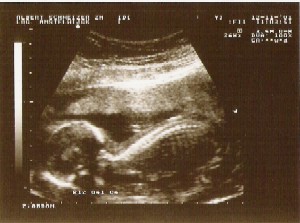

Het hoofdje van je baby heeft inmiddels de juiste verhouding gekregen met de rest van het lichaampje.

Hij heeft al een duidelijke gezichtsuitdrukking. De 40 weken worden namelijk gerekend vanaf je laatste menstruatie. Lengte van je baby:.

Je kind heeft een eigen slaap- en waakritme. Download this image for free in High-Definition resolution the choice "download button" below. 10 -13 weken zwanger.